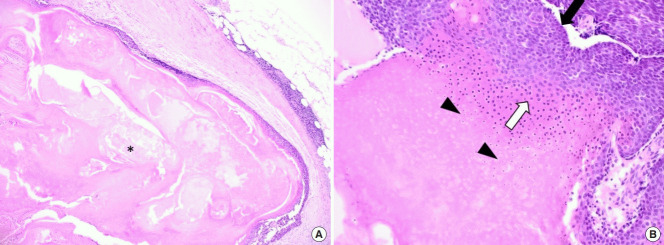

毛母质瘤是一种良性皮肤肿瘤,起源于分化为毛母质细胞的表皮原始基底细胞。 大多数毛母质瘤的直径约为 1 厘米,而直径为 5 厘米或以上的则被归类为巨大毛母质瘤。 头颈部毛母质瘤的鉴别诊断包括皮脂腺囊肿、骨化性血肿、鳃残余、耳前窦、淋巴结肿大、巨细胞瘤、软骨瘤、皮样囊肿、退化性纤维黄瘤、异物反应、皮肤骨瘤。 正确诊断毛母质瘤需要放射影像学和组织病理学检查。 其组织病理学特征包括外围的细胞簇(包括有核基底样细胞)和中心的无核影细胞(也称为“鬼细胞”)呈圆形排列。 巨大的毛母质瘤通常与外伤有关,并且有时会在外伤事件后观察到溃疡或坏死组织物质的局灶性经表皮消除。